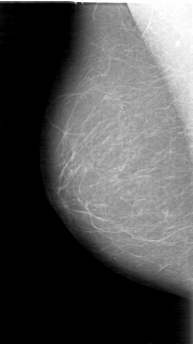

D_4048_1.LEFT_CC

LEFT_CC LINES 5356 PIXELS_PER_LINE 2581 BITS_PER_PIXEL 12 RESOLUTION 43.5 OVERLAY

FILE: D_4048_1.LEFT_CC.OVERLAY

TOTAL_ABNORMALITIES 1

ABNORMALITY 1

LESION_TYPE MASS SHAPE IRREGULAR MARGINS OBSCURED

ASSESSMENT 0

SUBTLETY 5

PATHOLOGY BENIGN

TOTAL_OUTLINES 1

BOUNDARY